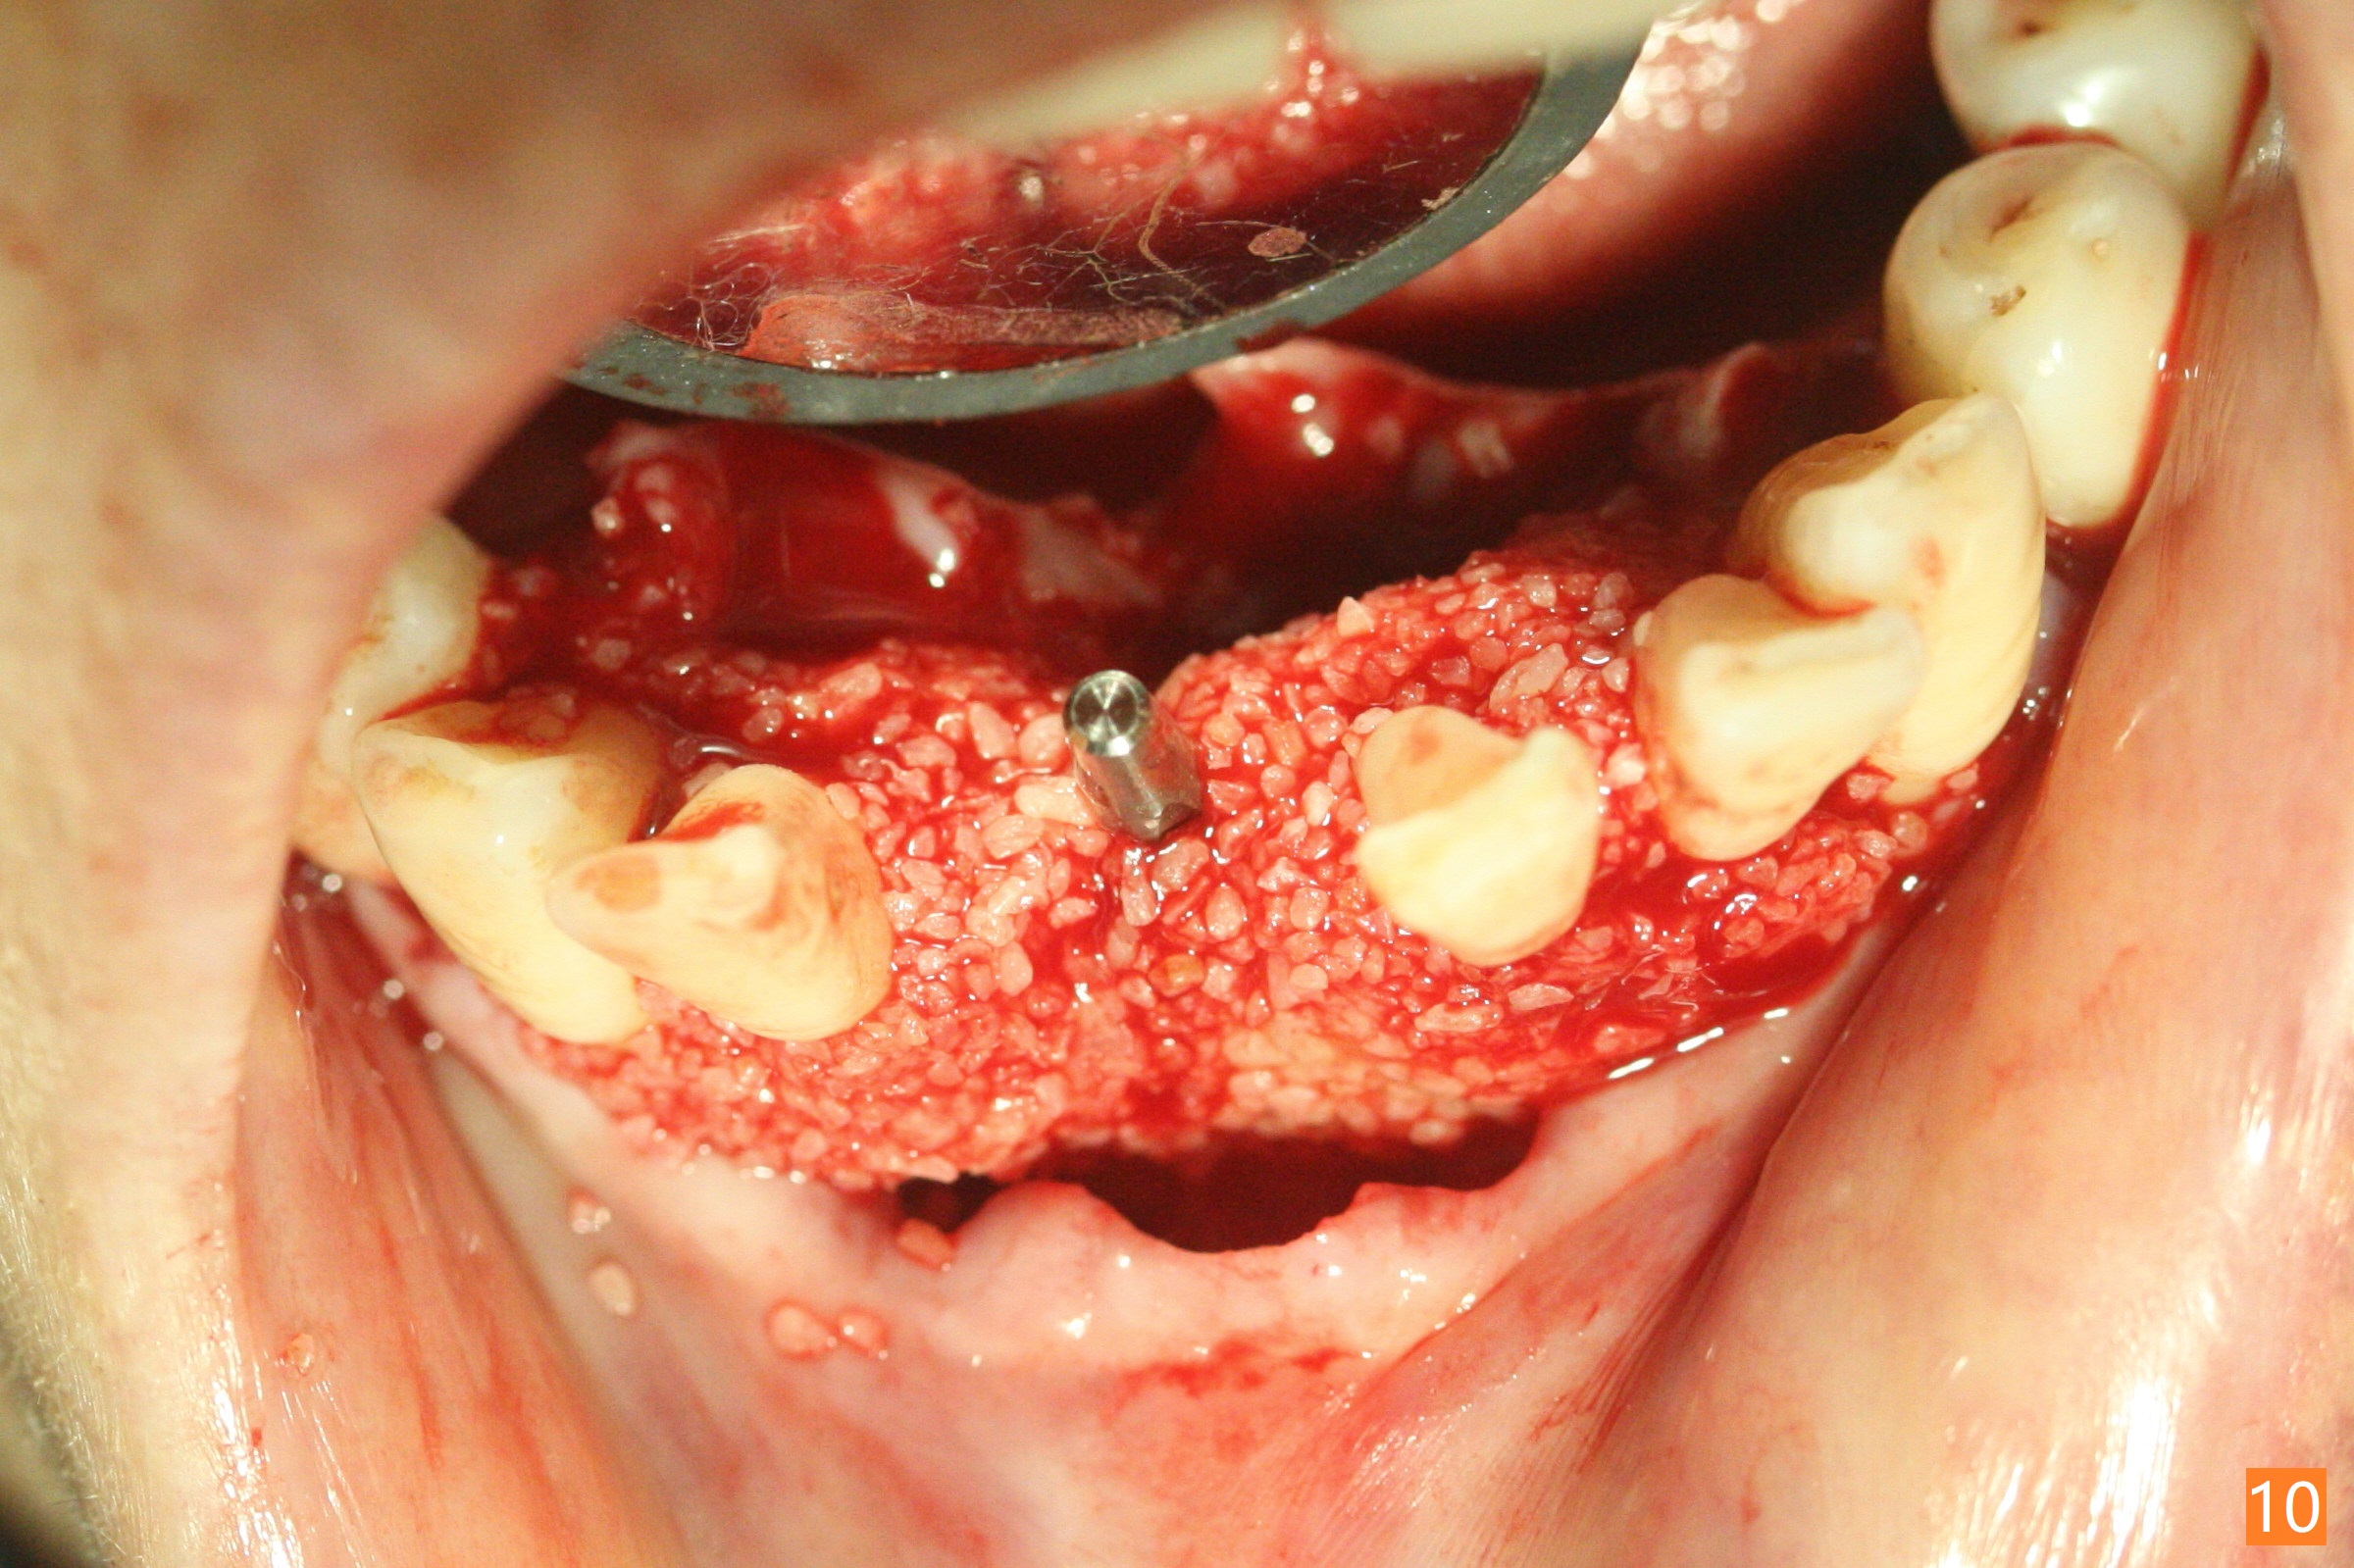

56岁女十分恐惧治疗,缺失右下1,其余切牙由于骨质吸收颊侧移位(图一:1,2),但是她不愿意拔除,同意右下1种植,牙周骨手术,植骨;植体整合后作为支抗,矫正移位下门牙。为了防止忘记舌侧瓣分离,先做舌侧切口(图二),然后颊侧瓣松弛分离(图三),包括使用前牙隧道刀(图四)切断颊侧骨膜,松弛到颊侧瓣能向舌侧牵拉3-4毫米(图五),舌侧瓣骨膜下广泛,深部分离(好像不能切断骨膜,图六),放置导板,磨平狭窄的牙槽嵴(图七:O(osteotomy)),植入2.5x12(4)毫米一段式植体(图八:故意舌侧植入,以便以后矫正),在颊侧骨板打多个出血洞(图八:箭头),然后把在平的器皿上形成的粘性骨板(sticky bone,图九),放置于植体和移位切牙周围(图十),接着使用消毒过的橡皮障punch(图十一(纸头相当于PRF膜;事先给助手示范))在三个PRF膜(图十二)打洞,套在植体和门牙上(图十三: 箭头),防止膜(图十四)和骨块(图十五,十六:*)移位,最后还必须使用最原始方法牙周敷料保护伤口(图十七)。术后9天,舌侧牙周敷料脱落,伤口稍微裂开(图十八)。术后18天撤除敷料,伤口裂开处有新鲜肉芽组织生长(图十九(*:下面是填入的骨粉,将是增宽的牙槽嵴(如果你是乐观主义者)),二十)。病人十分感激我们帮助她度过难关。她的确有sleep apnea,否定tongue thrust。术后三个月植体周围没有明显骨质吸收(图二十一至二十三),左下1,2轻度反合(图二十四),植体周围软组织健康(图二十五),5-5安置矫正器(图二十六,二十七,12 niti)。一周后下切牙向舌侧移动(图二十八),左下1,2反合纠正(图二十九)。再一周变化不大(图三十),植牙圈有些松动,两周后将重做临时牙冠,槽往舌侧移动。结果病人提前回来,植牙槽舌侧移位。一周后右下2不适(图三十一),尝试近中牵引(图三十二)。